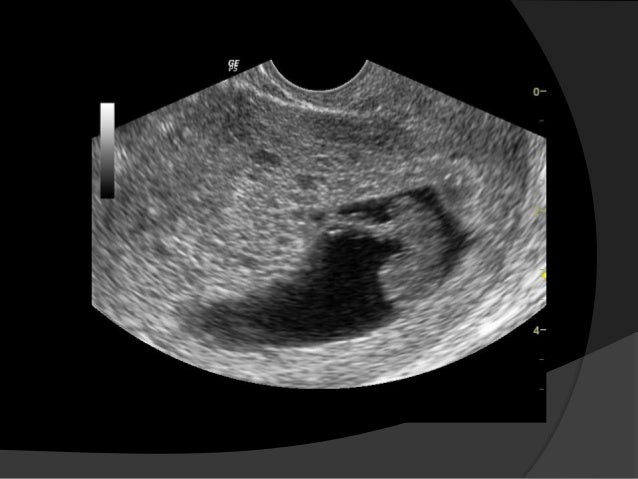

Ultrasound in early pregnancy (before 12 weeks) - Dating Scan Dating ultrasound A 'dating ultrasound' or 'dating scan' is a scan done early in pregnancy (before 12 weeks) . It is usually done to check how many weeks pregnant you are and therefore to calculate the estimated due date, but it can be done for other reasons . Only a few women need a dating scan .

The earlier in pregnancy a scan is performed, the more accurate the age assignment from crown-rump length . The initial age assignment should not be revised on subsequent scans 5 . Overall, the accuracy of sonographic dating in the first trimester is ~5 days (95% confidence range) .

Overall, the accuracy of sonographic dating in the first trimester is +/-5 days (95% confidence range) . Cardiac activity should be present in an embryo with a CRL β₯7 mm 3 . If it not detected at this size on transvaginal scanning performed by an experienced operator, it is an indicator of failed early pregnancy (missed miscarriage) .